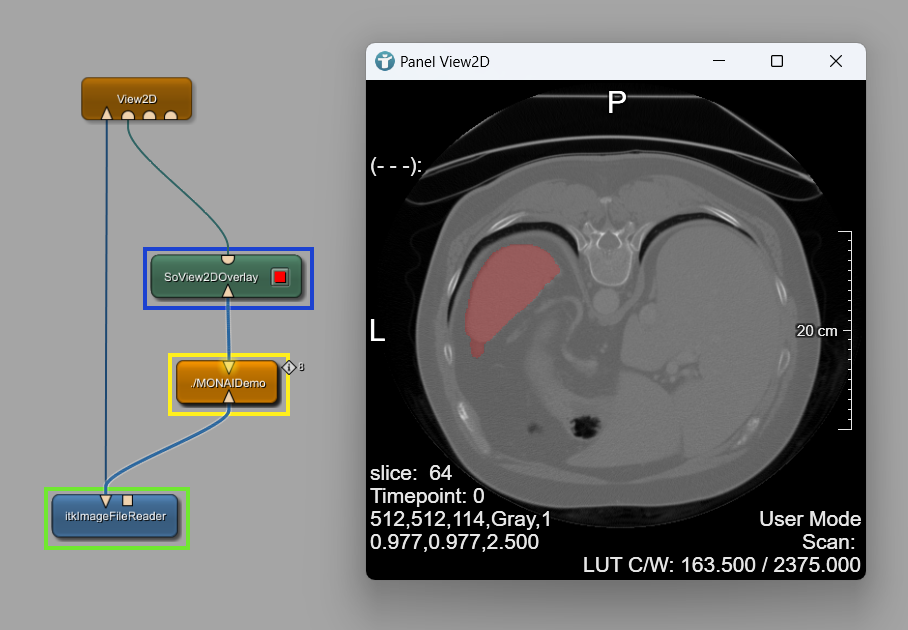

Connect the module to your local macro module MONAIDemo. The result of the segmentation shall be visualized as a semitransparent overlay on your original image.

Add a SoView2DOverlay and a View2D module and connect them to your local macro module MONAIDemo.

The results are shown as a semitransparent overlay.